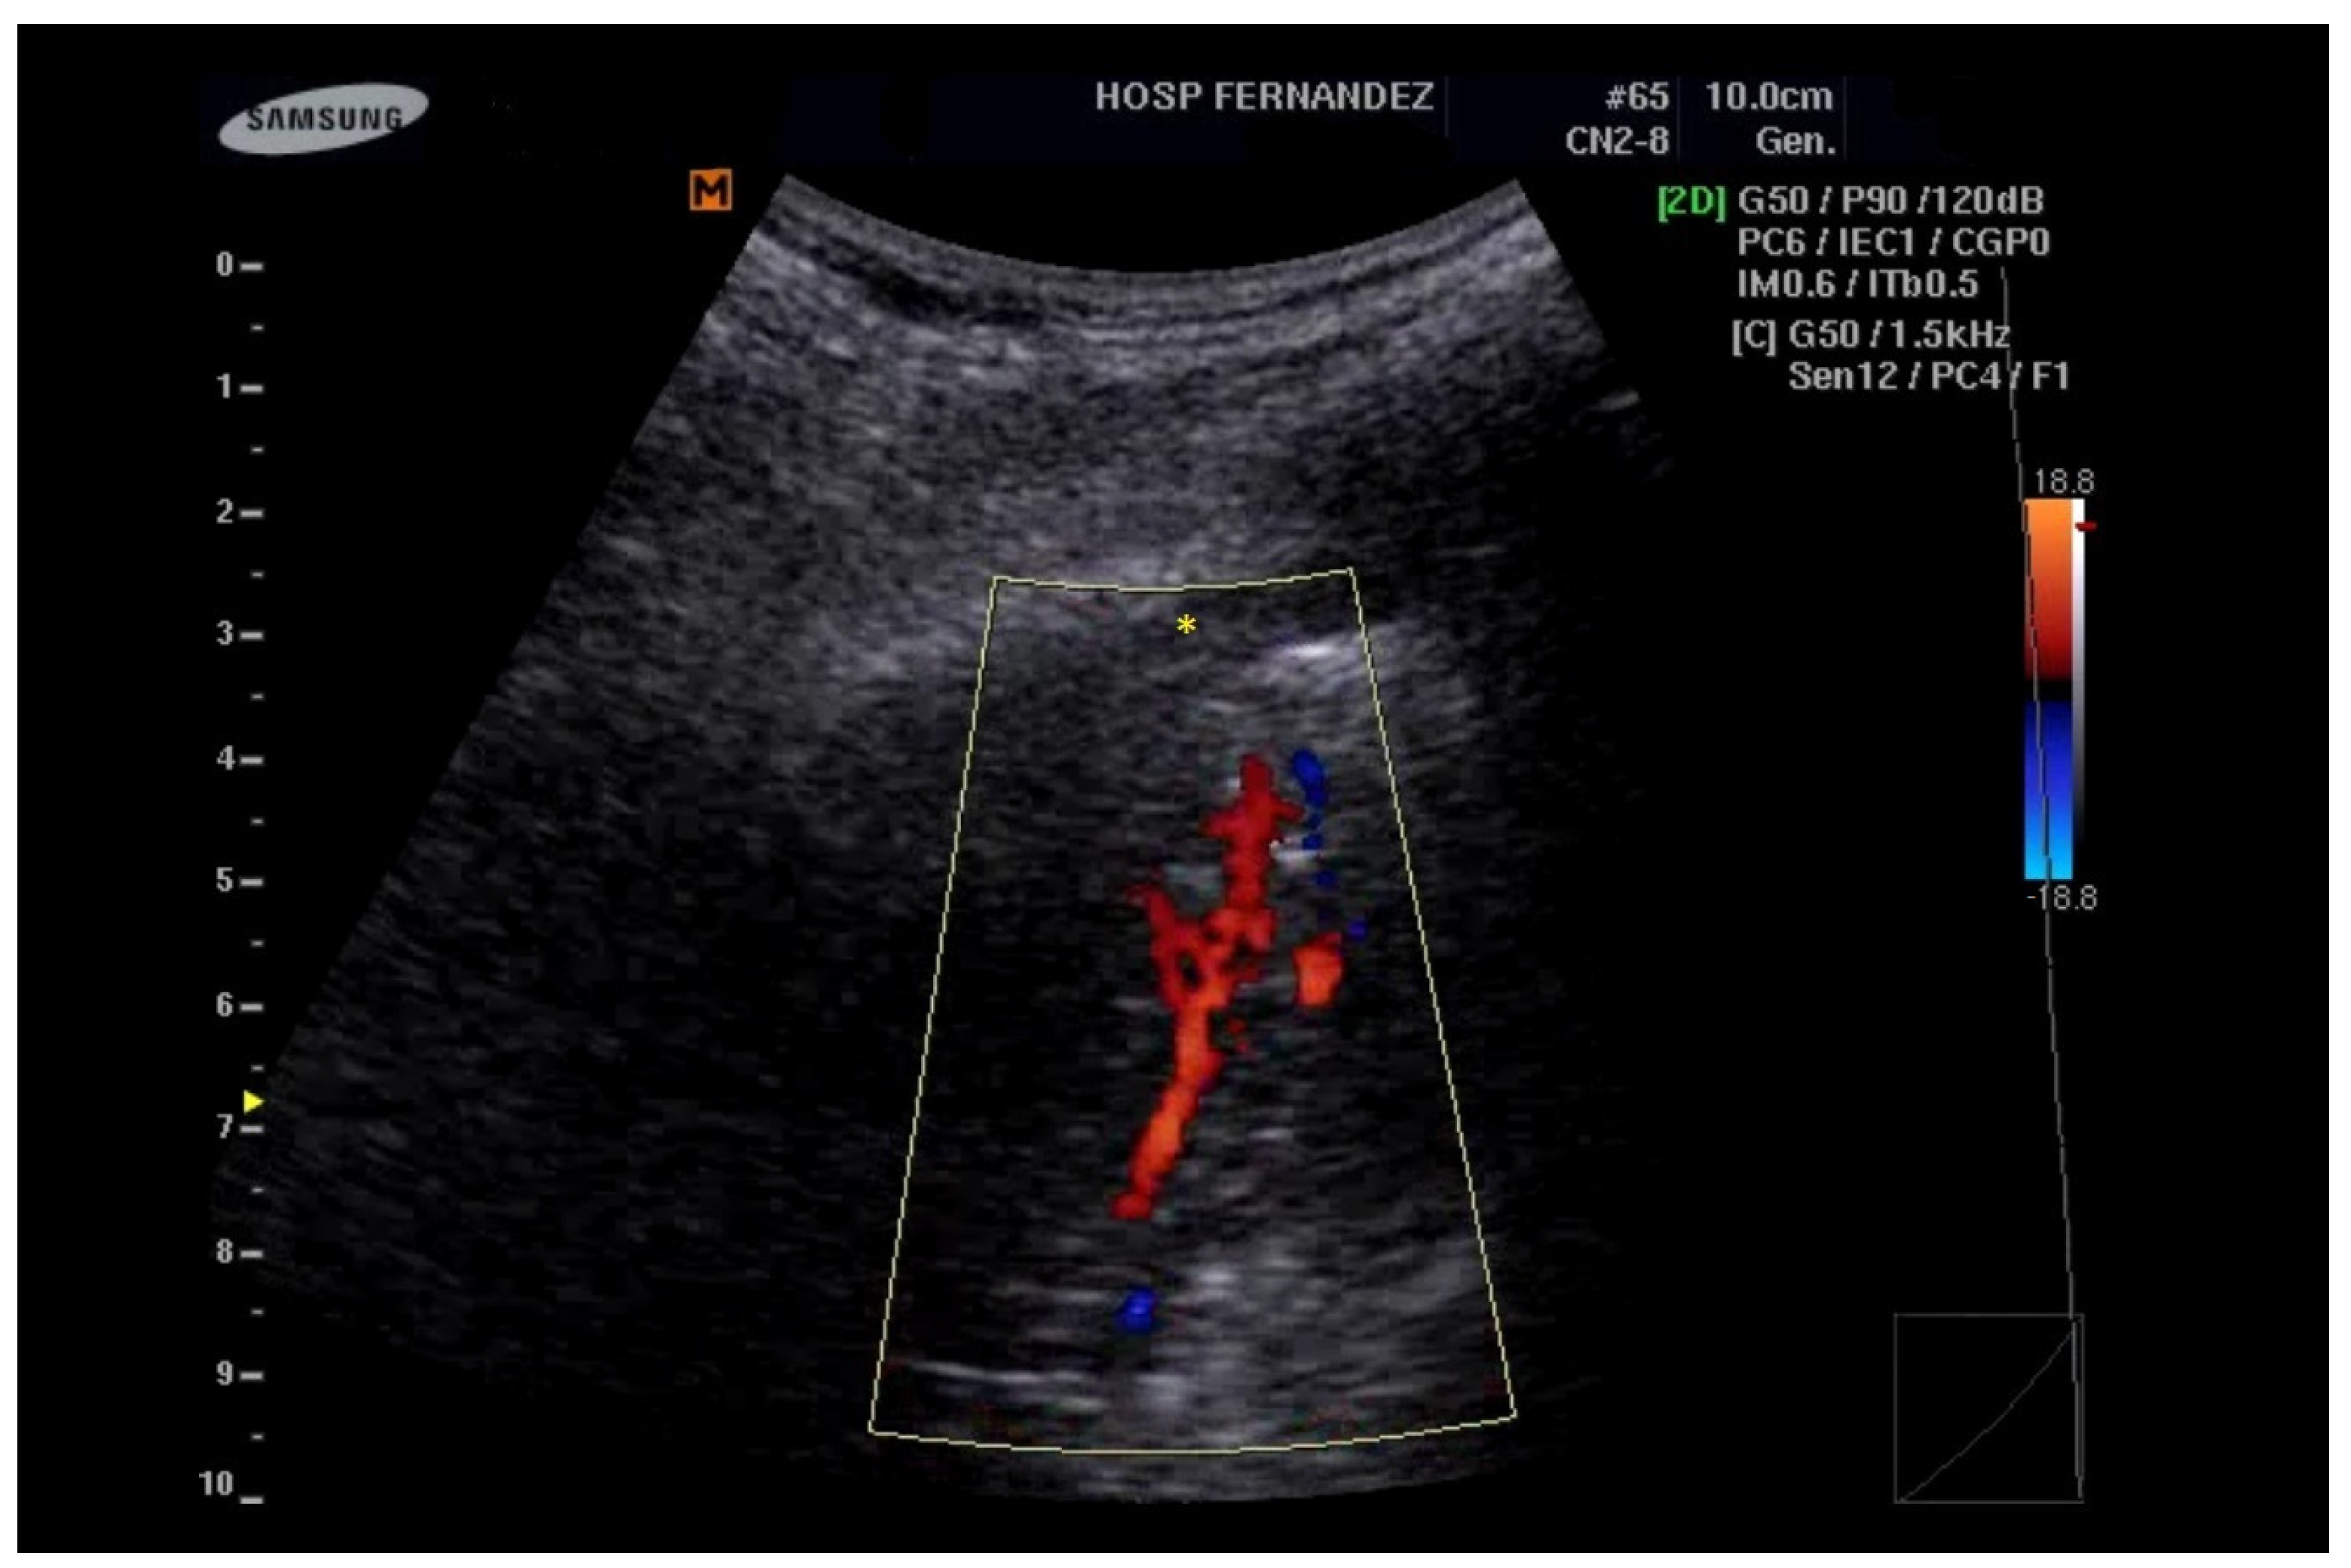

Figure 4.

Consolidations with an LUS score of 3 indicate a complete loss of aeration measuring greater than 2 cm (yellow *). In addition, the preservation of the vasculature can be detected by color Doppler.

The following supporting information can be downloaded at https://www.mdpi.com/article/10.3390/healthcare13101148/s1, Clip S1: B-lines are hyperechoic artifacts descending from the pleural line to the bottom of the screen (yellow *); Clip S2: Multiple B-lines and irregular pleural line (yellow * and yellow ↓); Clip S3: Subpleural consolidation (yellow ↓) “Shred sign”; Clip S4: Consolidations with an LUS score of 3 indicate a complete loss of aeration measuring greater than 2 cm (yellow *). In addition, the preservation of the vasculature can be detected by color Doppler. Clip S5: Consolidations with an LUS score of 3 indicate a complete loss of aeration of the entire inferior right lobe (yellow *).